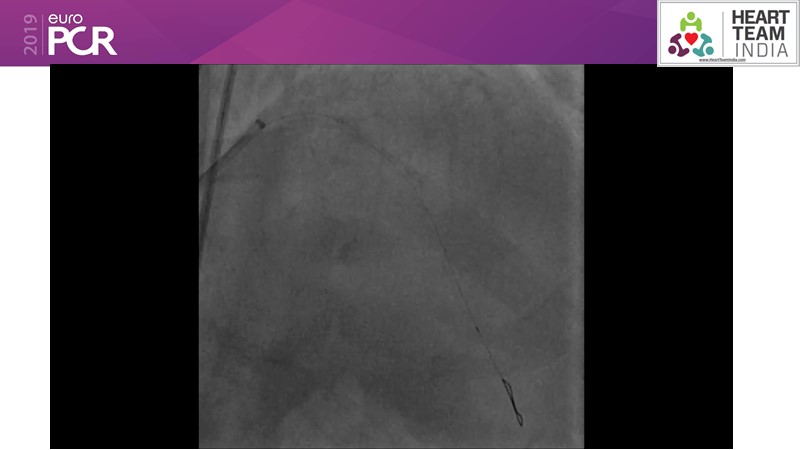

Ability to treat diabetic patients: DES + DCB strategy

Consult this session to get insights about the need for a dedicated drug eluting stent (DES), as well as the benefits of a DES+DCB strategy, for diabetes mellitus (DM) and acute MI (AMI) patients.

- To understand and learn benefits of DES+DCB strategy to provide uniform and homogenous drug delivery in patients with diabetes mellitus and acute MI